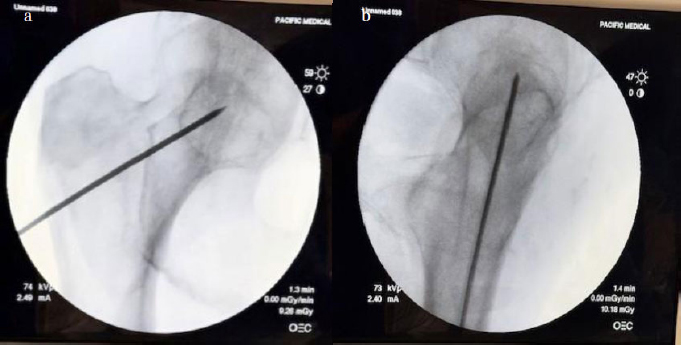

Four human cadaveric hips were examined: 86M, 82F, 77M, and one of unknown age and sex. Under plain fluoroscopy, the specimens did not appear osteoporotic. A standard arthroscope (Stryker) was used for visualization of the femoral neck intramedullary cavity. A guidewire was introduced into the femoral neck under biplanar fluoroscopy and was kept centered in both planes (Fig. 1a, b).

AP and lateral fluoroscopic views with guide wire. The starting point was above the lesser trochanter in the coronal plane.

Next, a 5 mm reamer was used to create a path for the 4 mm arthroscope. The cavity was irrigated, and loose cancellous bone and marrow contents were removed. A second portal was created approximately 3 mm inferior to the first (still above the lesser trochanter), through which a 3.5 mm Stryker shaver was introduced (Fig. 2).

Arthroscope and shaver in place under fluoroscopy.